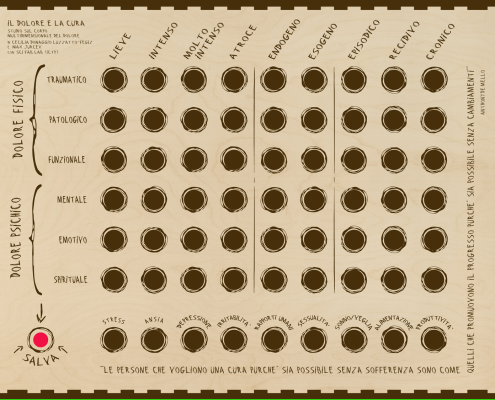

Dolore e cura- il corpo multidimensionale dl dolore, installazione di Cecilia Donaggio, in questa data l’artista produrrà una performance con la collaborazione di Betta Porro. Ore 18.30

L’artista affronta con coraggio un tema universale, ma mai forse trattato attraverso una analisi personale con i linguaggi dell’arte, quello del dolore. Parte da un’esperienza personale, dal suo dolore provocatole da una malattia autoimmune. S’interroga sulla funzione del dolore, quella di stimolare una ricerca per il cambiamento? Misurare o meglio “decostruire” il dolore permette di riascoltarsi, visualizzare il proprio dolore permette di “fare ordine”. Nel cambiamento, considerato come un’opportunità, è contenuta la cura. Dopo uno studio attento e prolungato l’artista è riuscita a presentare un misuratore multidimensionale del dolore configurabile come un pannello interattivo “analogico”con 63 fori correlati ad altrettante definizioni del dolore provato. L’inserimento dei tubetti di farmaci analgesici provoca l’attivazione degli interruttori del circuito elettronico (realizzato con la collaborazione di Carlo Fonda (fablab ICTP). Poter dare una misura al proprio dolore significa dargli un corpo, ed è il primo passo della cura che risiede comunque nella ricerca profonda di se stessi.